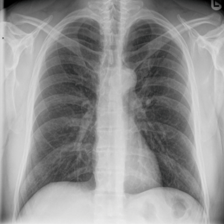

To pre-train a high-performance X-ray foundation model, the first thing we need to do is the collection of large-scale X-ray images. Therefore, a large-scale and high-resolution dataset that contains X-ray medical images is collected for the pre-training. Some representative samples are visualized in Fig. 3.